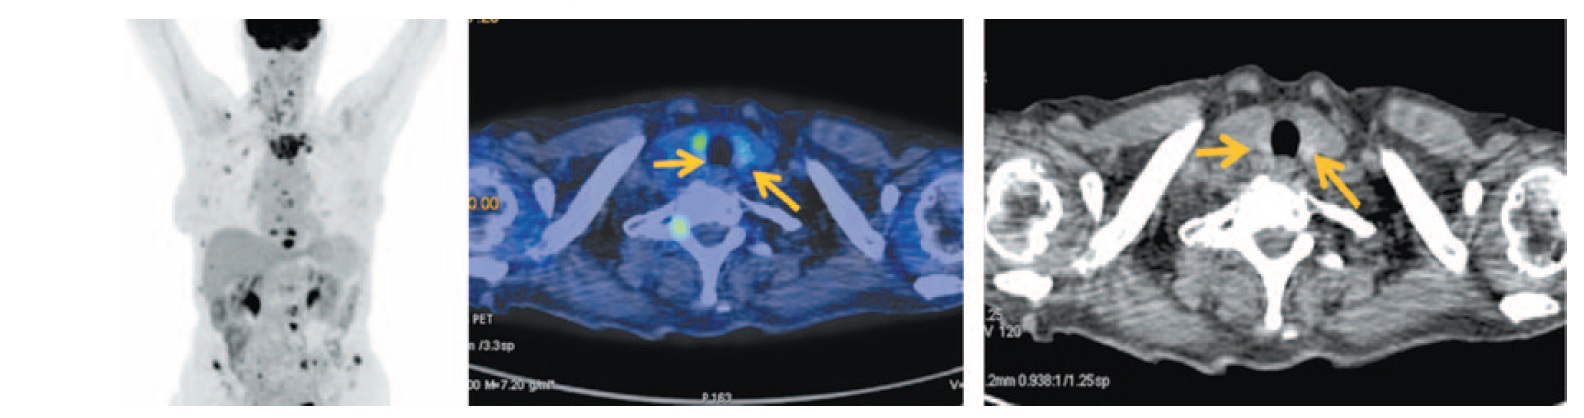

Для установления распространенности опухолевого процесса выполнена ПЭТ/КТ с 18-ФДГ. Определяется увеличение объема щитовидной железы с повышенной фиксацией РФП, стандартизированный коэффициент максимального накопления, SUVmax составил 6,3. Плотность ткани железы снижена. Определяются множественные мелкие, до 6 мм, яремные лимфатические узлы слева II–V групп с диффузной фиксацией РФП, SUVmax 2,35 (рис. 9).

Рис. 9. Больная К., 55 лет. На MIP и аксиальных ПЭТ/КТ проекциях в щитовидной железе с двух сторон определяется увеличение объема ткани с повышенной фиксацией РФП, SUVmax 6,30, плотность ткани снижена, справа метаболическим размером до 29×39×52 мм, слева до 38×48×43 мм, контуры нечеткие. / Fig. 9. A 55-year-old woman. MIP and axial PET/CT images show the enlargement of the thyroid gland tissue on both sides with increased RFP uptake, SUVmax 6.30, the density of tissue is decreased on the right measuring 29×39×52 mm and on the left measuring 38×48×43 mm, the margins are fuzzy.

В левой молочной железе на границе верхних квадрантов определяется узловое образование размером 20×23 мм с повышенной фиксацией РФП. Полисегментарно в легких с двух сторон определяются очаговые образования размером до 6 мм. На фоне инфильтрированной клетчатки слева определяются аксиллярные лимфатические узлы размером до 26×12 мм с повышенной фиксацией 18-ФДГ, SUVmax 3,52 (рис. 10).

Рис. 10. Больная К., 55 лет. На аксиальных ПЭТ/КТ проекциях на границе верхних квадрантов левой молочной железы определяется узловое образование размером до 20×23 мм с повышенной фиксацией ФДГ с SUVmax 6,19 с четким неровным контуром, однородной плотности. / Fig. 10. A 55-year-old woman. Axial PET/CT images show a lump measuring 20×23 mm in the border in the upper quadrants of left breast with increased FDG uptake SUVmax 6.19 with clear rough margins and homogeneous density.